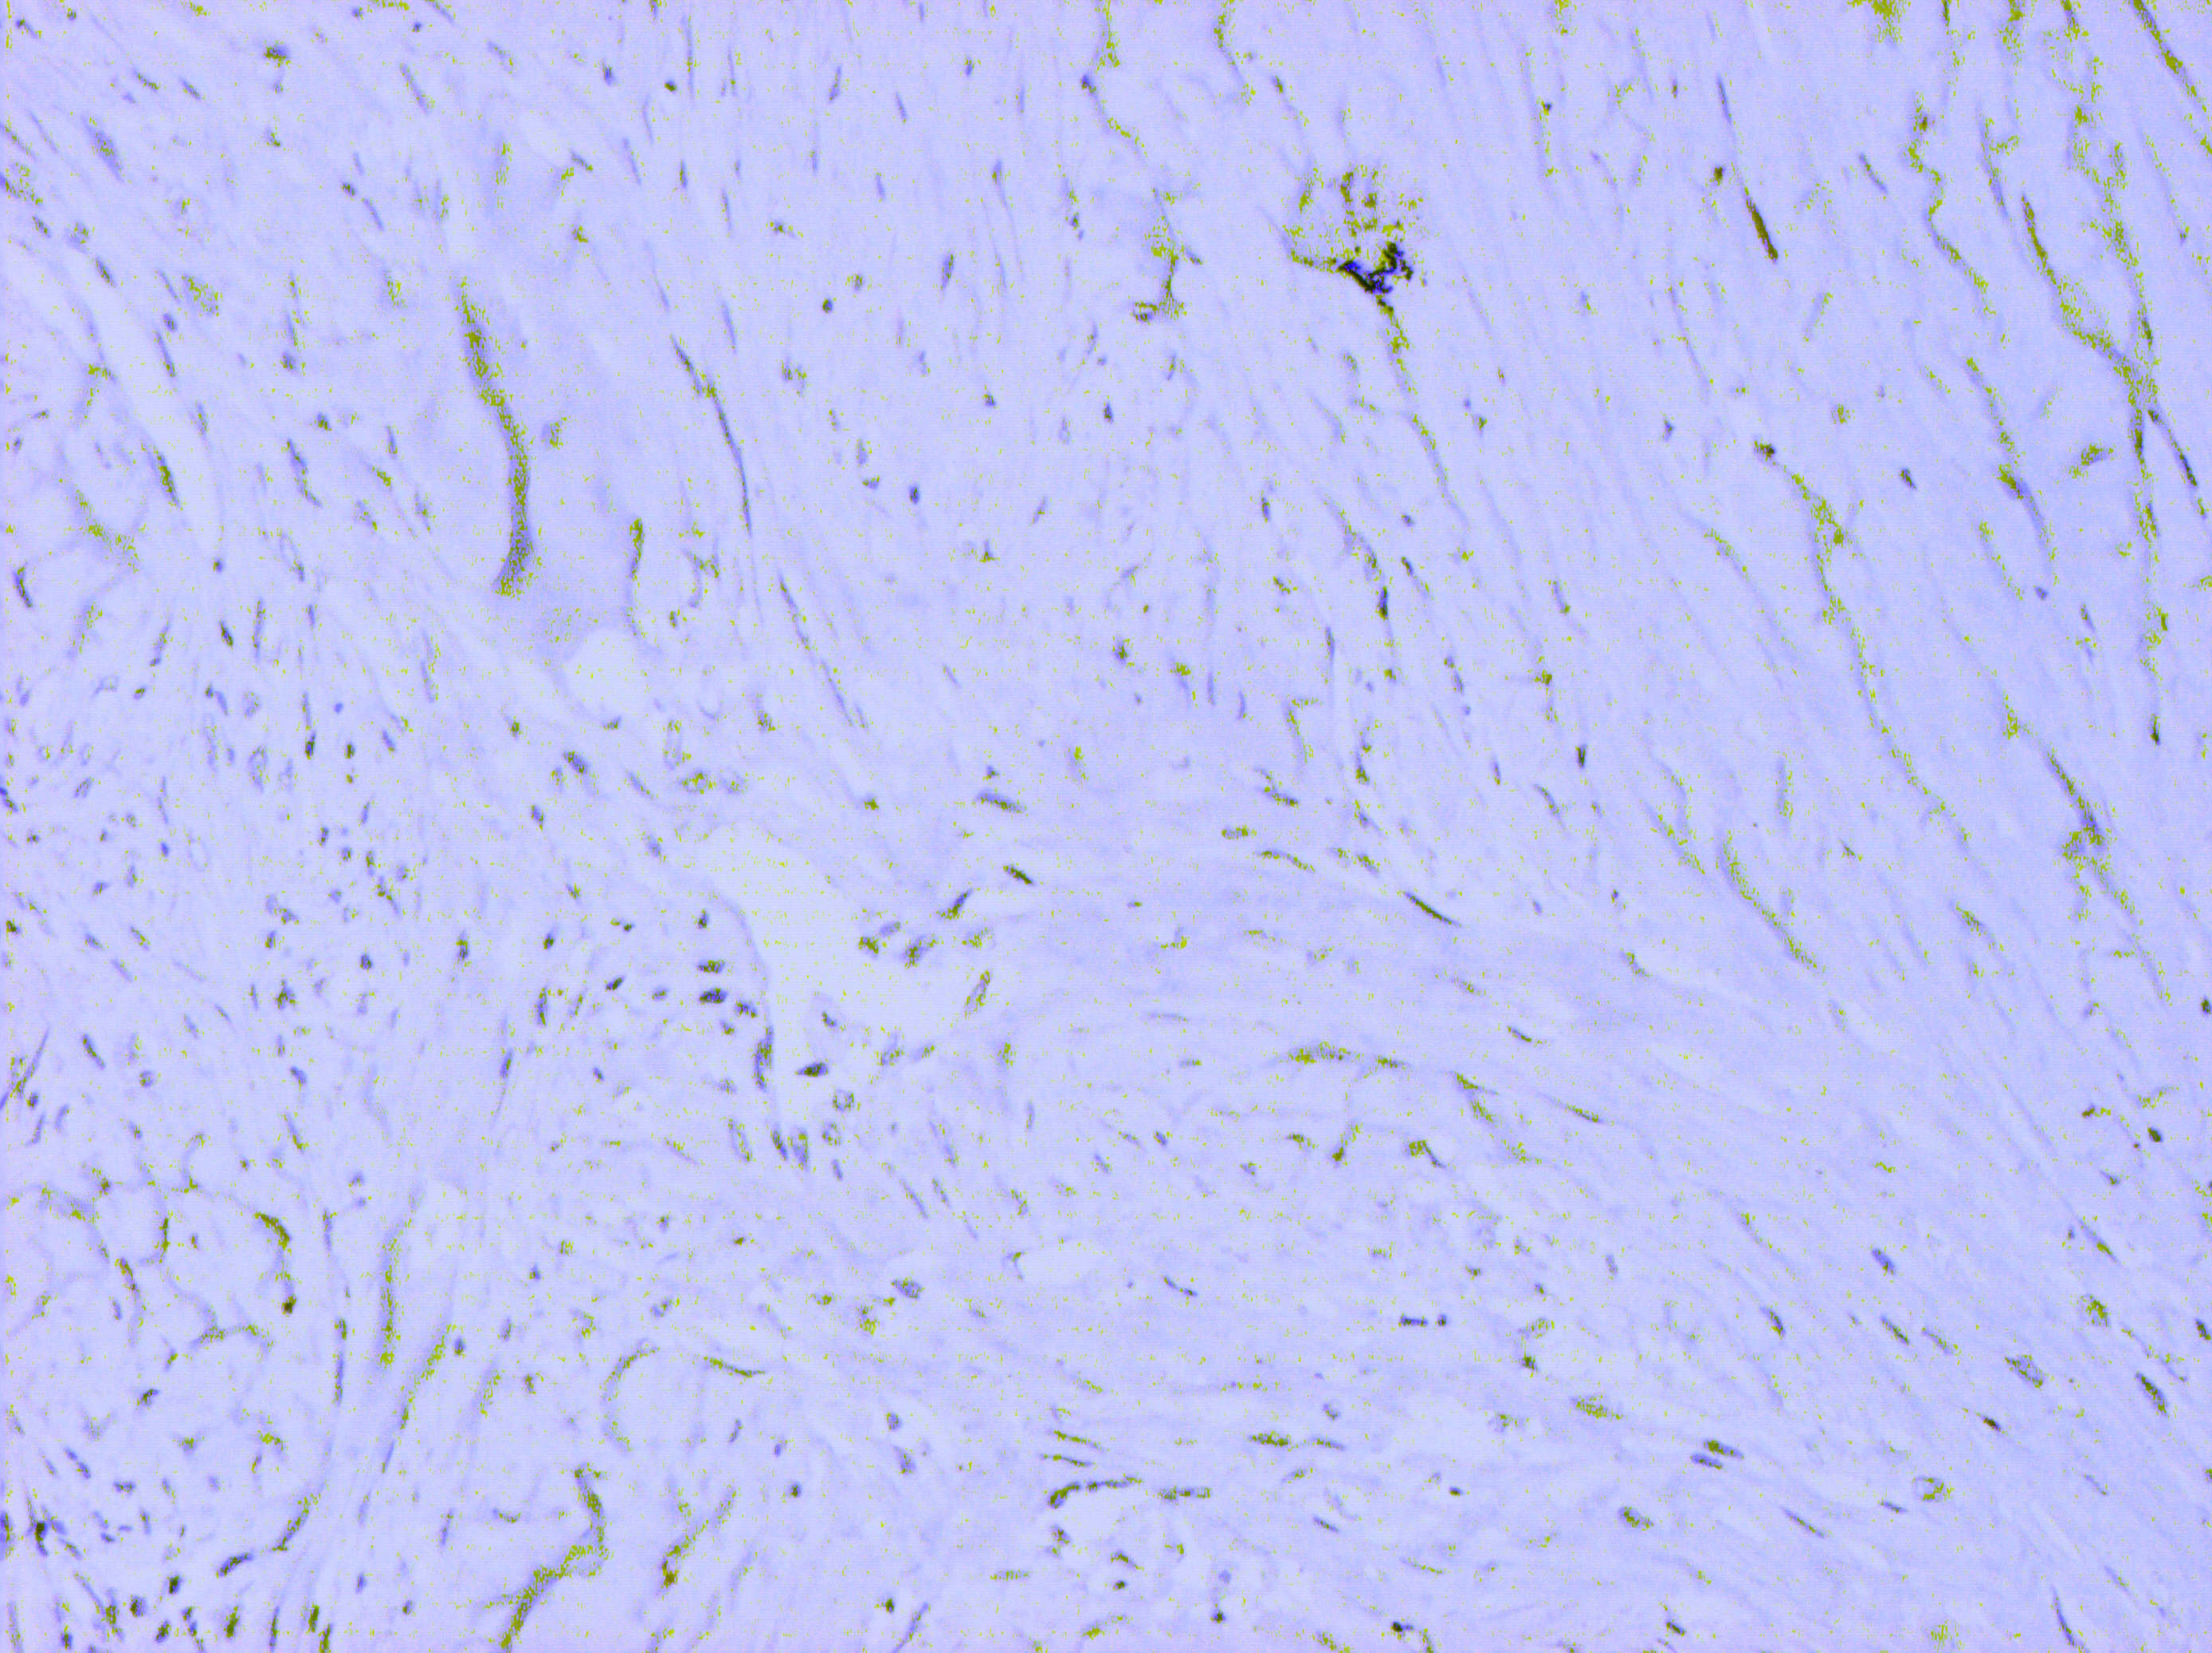

Матеріали та методи. Для ІГХ-дослідження було відібрано 60 парафінових блоків пухлин, у яких гістологічно було верифіковано діагноз саркоми (42) та філоїдної пухлини (18). ІГХ-дослідження проводили з використанням спектра відповідних антитіл, який включав маркери панцитокератинів (клон AE1/AE3); ERG (клон EP111); SOX-10 (клон EP268); TLE1 (клон 1F5); кальдесмону (клон h-CD); міогеніну (Myf-4) (клон F5D); MyoD1 (клон EP212); десміну (клон D33); MDM2 (клон 1B10); CDK4 (клон EP180); CD68 (клон PG-M1); CD34 (клон QBEnd 10); CD31 (клон JC70A); бета-катеніну (клон betaCatenin-1); гладеньком’язового актину альфа (клон 1A4); актину (клон HHF35); епітеліального мембранного антигену (EMA, MUC1) (клон E29). Також визначали рівень експресії маркера проліферації Ki-67 (клон MIB-1). Дослідження проводили в лабораторії CSD Health Care, м. Київ.

Результати дослідження та їх обговорення. Після проведених імуногістохімічних досліджень виявилось, що із 12 сарком без уточненого гістотипу в 9 випадках були плеоморфні саркоми, у 2-х – міофібробластні саркоми, та одна остеосаркома. Із 27 блоків ангіосарком імуногістохімічно було підтверджено 17 (63,0 %), інші 10 (37,0 %) виявились карциномами. Фібросаркоми (три гістологічні блоки) були повністю підтверджені імуногістохімічно. Серед 18 гістологічних блоків філоїдних пухлин проміжного типу у двох випадках (11,1 %) було встановлено злоякісний варіант ФП.